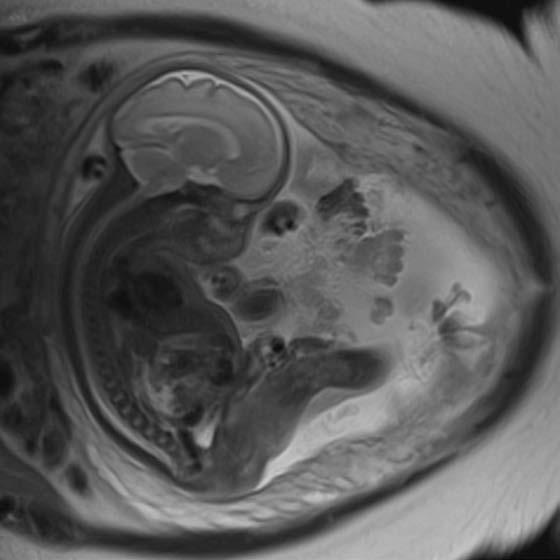

When an unborn baby has an abnormality, decisions about the delivery and neonatal care can often be planned in advance – with the help of an MRI.

MRI image acquisition can be tricky and quality reporting is an acquired skill. An expert in the field, Dr Lauren Raubenheimer honed her skills in London under world-renowned foetal and neonatal imaging specialist, Prof Mary Rutherford. Dr Raubenheimer joined SCP Radiology as a consulting radiologist.

As a mother herself, Dr Raubenheimer has a deep emotional investment in her work.

“When a couple discovers their baby has an abnormality, the impact is enormous,” she explains. “I hope my findings give parents more answers as they navigate a difficult path.” With the help of an MRI, Dr Raubenheimer says that in many cases, the timing and route of delivery, as well as the neonatal care required, can be planned in advance.

When would Foetal MRI be recommended?

Patients are typically referred from Foetal Medicine

Specialists after an abnormality has been detected on a screening ultrasound. An MRI can be done to confirm the abnormality, as well as to assess for abnormalities that are not readily visible through standard imaging techniques. This can significantly affect the prognosis. A foetal MRI can be performed either in the second or third trimester.

Dr Raubenheimer’s special interest is in developmental foetal brain abnormalities, but she also performs MRIs for body abnormalities, including congenital diaphragmatic hernia and spina bifida.

MRI can be superior to ultrasound in certain instances, such as assessing the folding of the brain and parts of the brain obscured by the skull, when amniotic fluid is low and when mothers have a high body mass index (BMI).

Foetal movement used to be an obstacle in getting good quality MR images. However, with today’s advanced magnets and faster imaging sequences, excellent image quality can be obtained. At SCP Radiology, foetal MRI scans are done exclusively by lead MRI radiographer Andrea Nagel.

comes

Safety is, of course, of utmost importance. Dr Raubenheimer reassures us that present data shows no conclusively documented harmful effects of MRI imaging on the

developing foetus, providing it is at the safe and optimal level. She also adds that MRI does not use ionising radiation, and intravenous contrast is not administered in foetal MRI.

Foetal MRI is covered by medical aids, but pre-authorisation is required.

Dr Raubenheimer prefers that patients are referred from a Foetal Medicine Specialist after a detailed ultrasound. “Having access to ultrasound reports and knowing the exact gestation is crucial to an accurate MRI report,” she emphasises.